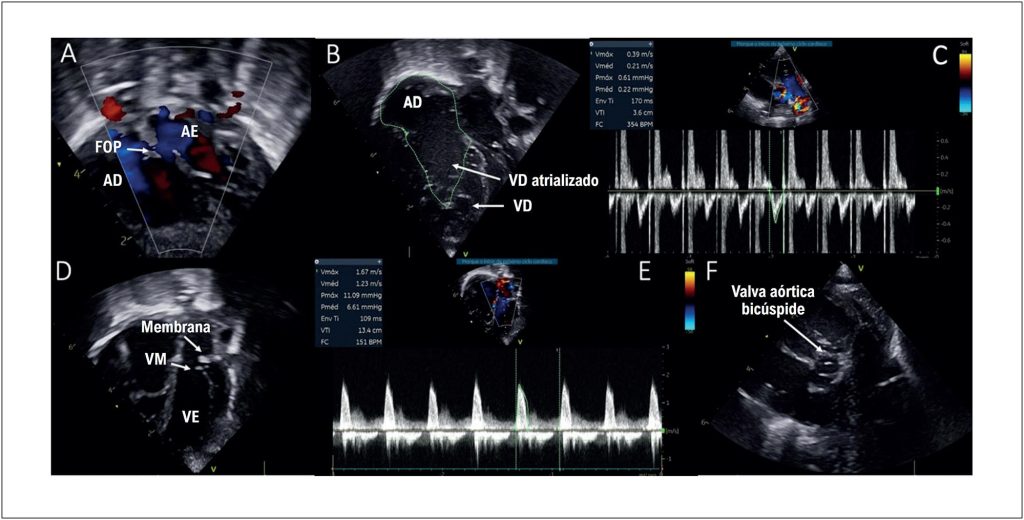

A anomalia de Ebstein é uma cardiopatia congênita complexa que ocorre em um a cada 200 000 nascidos vivos. Sua associação com lesões obstrutivas do lado esquerdo é condição rara e de difícil manejo clínico e cirúrgico. Neste relato de caso, apresentamos um paciente recém-nascido com anomalia de Ebstein associada à estenose supra valvar mitral e coartação da aorta (CoA), que foi submetido a cateterismo cardíaco para implante de stent pós-dilatável no istmo aórtico por via carotídea.